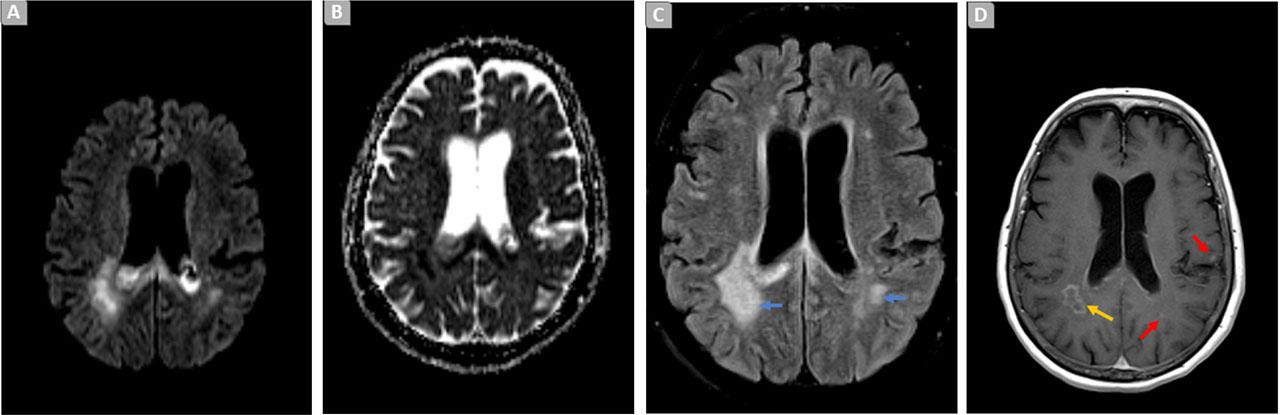

A follow-up microbiological study, conducted three weeks later, revealed the presence of a new strain of XDR Pseudomonas aeruginosa in a BRS, expressing in vitro resistance to Ceftolozane/Tazobactam (Table 1). MRI reassessment was suggestive of cerebritis with abscess formation in the right parietal region (Figure 2).

Brain MRI. Axial diffusion weighted image (A), ADC map (B), T2/FLAIR (fluid-attenuation-inversion-recovery) (C) and T1 SE post contrast (D), showing increased signal in T2iFLAIR image at the adjacent bilateral periventricular parenchyma [C, blue arrows], with restricted diffusion [A-B] and anomalous contrast enhancement [D], exhibiting signs of loculation in the right parietal white matter [D, yellow arrow] and some focal contralateral nodules [I), red arrows].